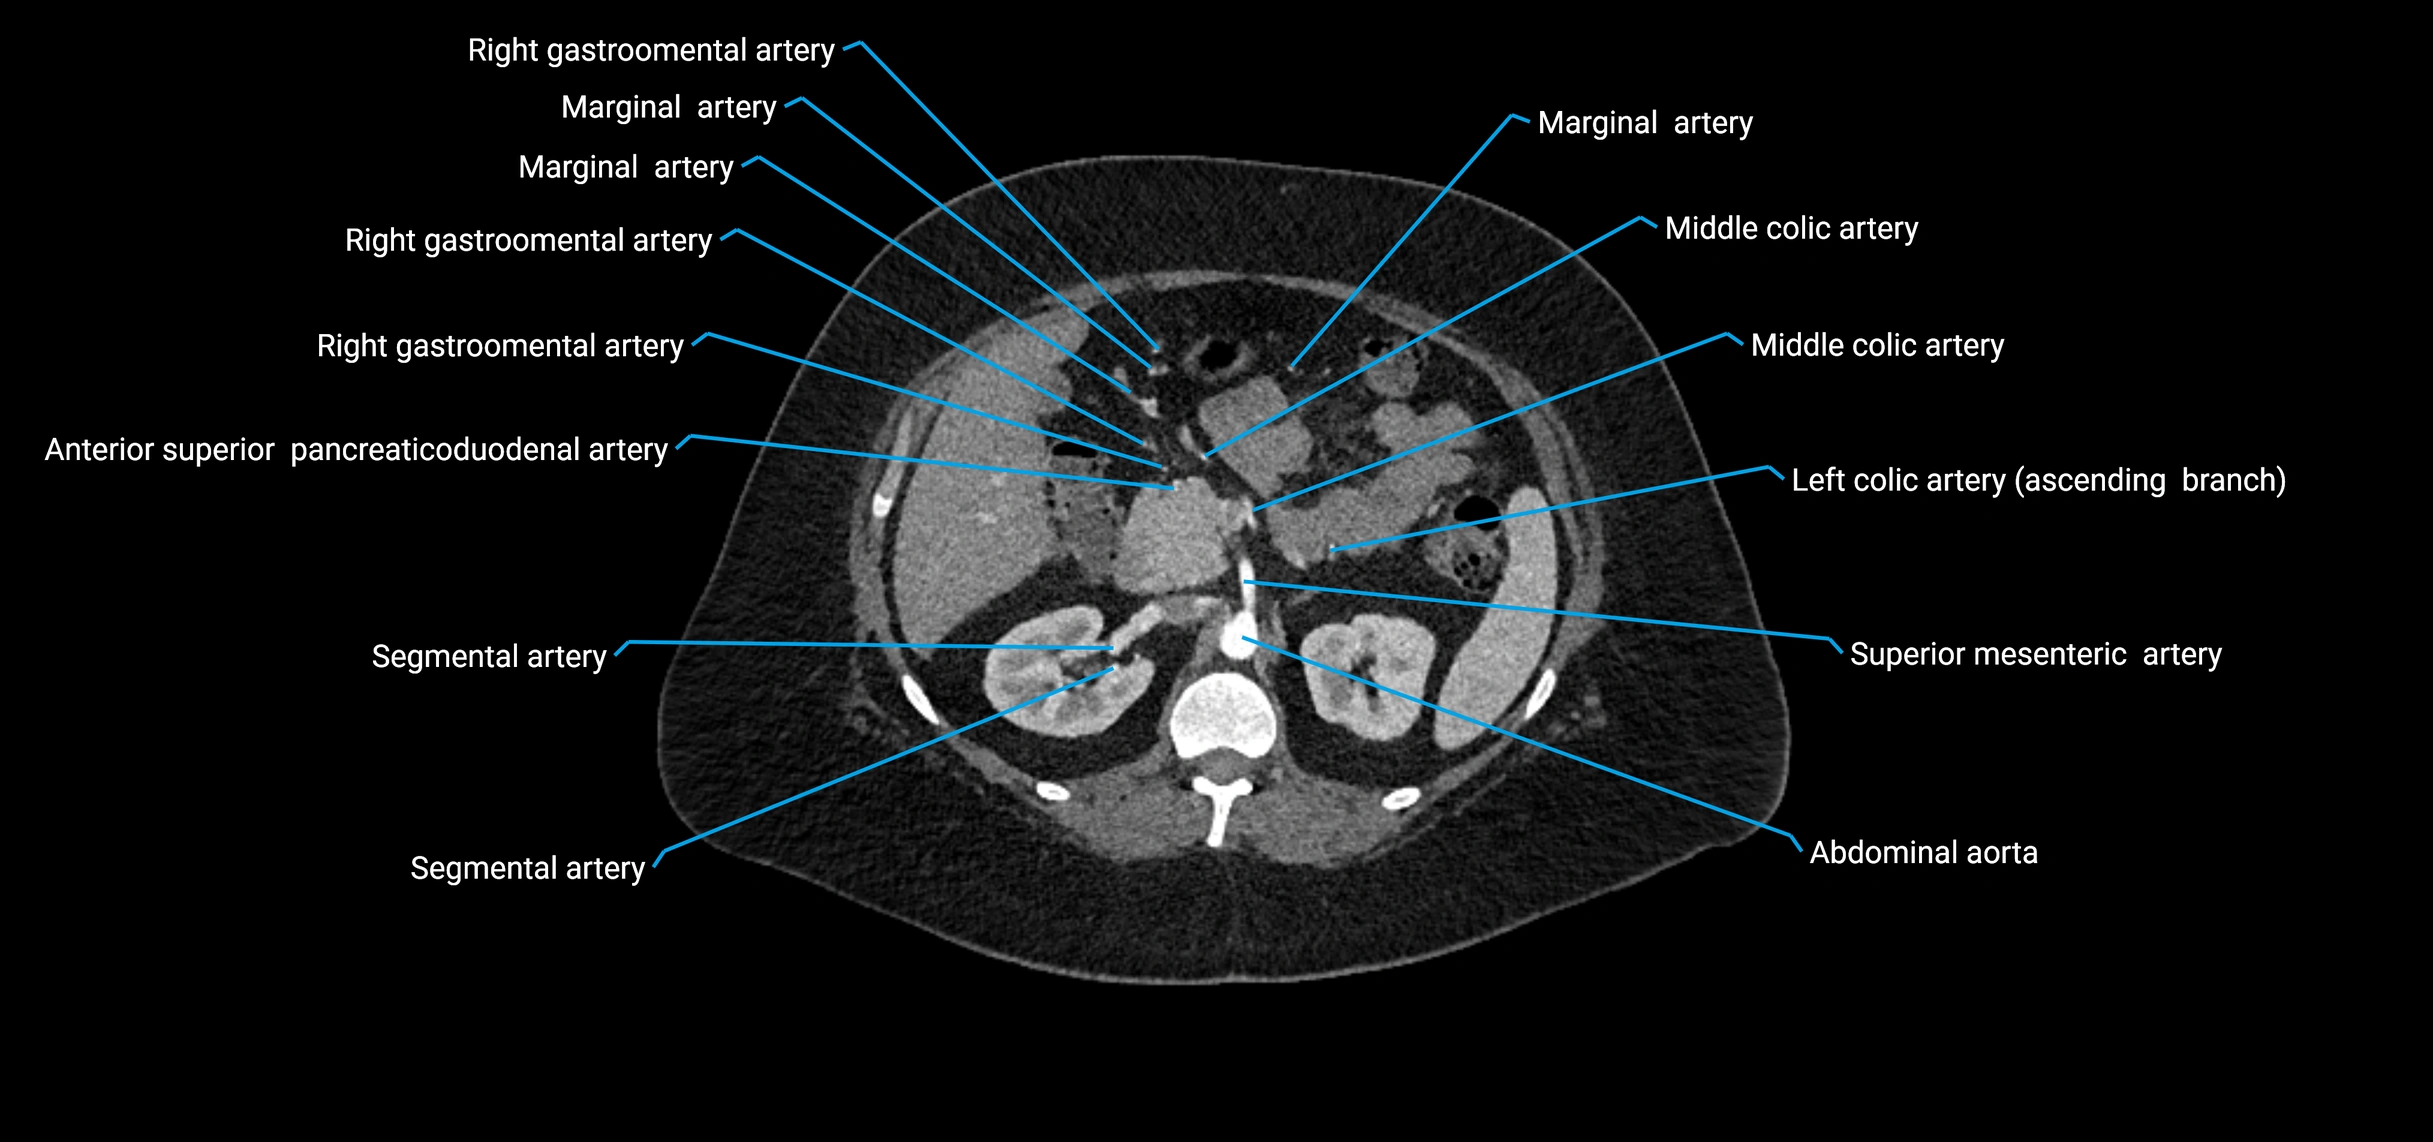

CT images

image

Contrast-enhanced CT (CTA):

• Gold standard for abdominal aortic imaging

• Provides excellent detail of lumen, wall, aneurysm, thrombus, and branch vessels

• Multiplanar and 3D reconstructions help in aneurysm measurement, stent graft planning, and dissection evaluation